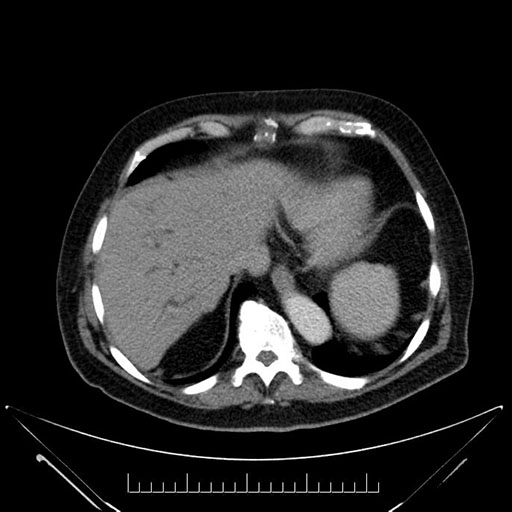

Imaging Analysis

Look through the patient's CT scan to identify any areas of concern for the necessary procedure.

Based on your CT findings, which issue(s) would give reason for "planned slowing down moment(s)" in this case?